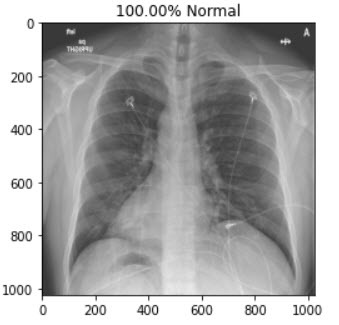

In this project ,we aim to propose a fully-automated method to detect/screen COVID-19 from the patient’s chest X-ray scanned images with out needing a clinical technician.

This is a demonstration of a cloud based AI Web Application which helps medical professionals or diagnostic centers to quickly screen/diagnoise the patient in just a single click.

I've teamed up with AI enthusiasts and got inspired from the several news articles to create a end to end web application using Deep learning.We have collected datasets from Mendeley and Qatar University which were posted on kaggle website.We augumented the images and trained the model to detect the hidden patterns in the images and using "Transfer Learning" approach we have used the model to deploy it on cloud platform and hooked it via flask server.